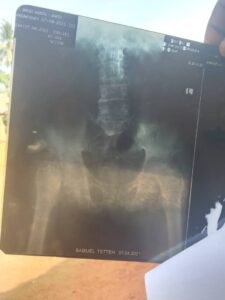

In a quiet, forgotten corner of the world, an elderly man lies in pain—weak, weary, and desperately in need of urgent medical care. 🧓🏾 His body, once strong and capable, is now failing him. Years of poverty, hardship, and neglect have left deep scars on his health. He suffers every day from chronic pain, untreated illness, and a growing condition that now requires life-saving surgery. 🏥💊

There is no one to turn to. No pension, no family, no government aid. Just silence… and suffering. 😔 He sleeps on a thin mat, barely eats once a day, and lives with the constant fear that his next breath could be his last. Yet somehow, he holds onto hope. 🌧️🕊️